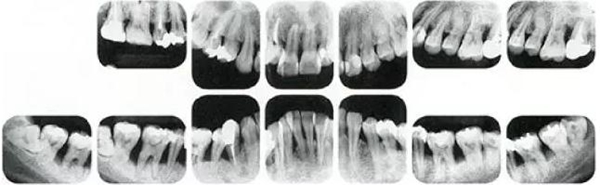

①的患者是35歲女性。4~10mm的牙周袋和大量的牙石。特別是在左上、右下、左下的磨牙處能看到大量牙槽骨吸收。這名患者是慢性牙周炎,僅在磨牙處有局部由風(fēng)險(xiǎn)因子導(dǎo)致(解剖學(xué)形態(tài))導(dǎo)致的重度病癥發(fā)展。

另一方面25歲女性的參考病例

②將會(huì)是什么樣的呢?左上、右下、左下的磨牙處有大量牙槽骨吸收,考慮到其發(fā)病年齡,斷定為是侵襲性牙周炎局部型。

但是實(shí)際上參考病例①和②是同名患者,①是②10年后的狀態(tài)。這名患者間隔10年后來(lái)就診,讓我們可以確認(rèn)到癥狀的變化。

●參考病例① 35歲女性

35歲女性。妊娠4個(gè)月。過(guò)去雖然接受過(guò)刷牙指導(dǎo),但菌斑控制狀態(tài)依然不理想?;颊哂邪l(fā)現(xiàn)自己刷牙時(shí)牙齦出血。

●參考病例② 25歲女性

25歲女性。菌斑控制狀態(tài)不好。齦溝除磨牙處外全在3mm以下,X光照片上左上、右下、左下的第一磨牙上有垂直性骨吸收。這個(gè)病例是參考病例①10年前的狀態(tài),是典型的侵襲性牙周炎局部型。